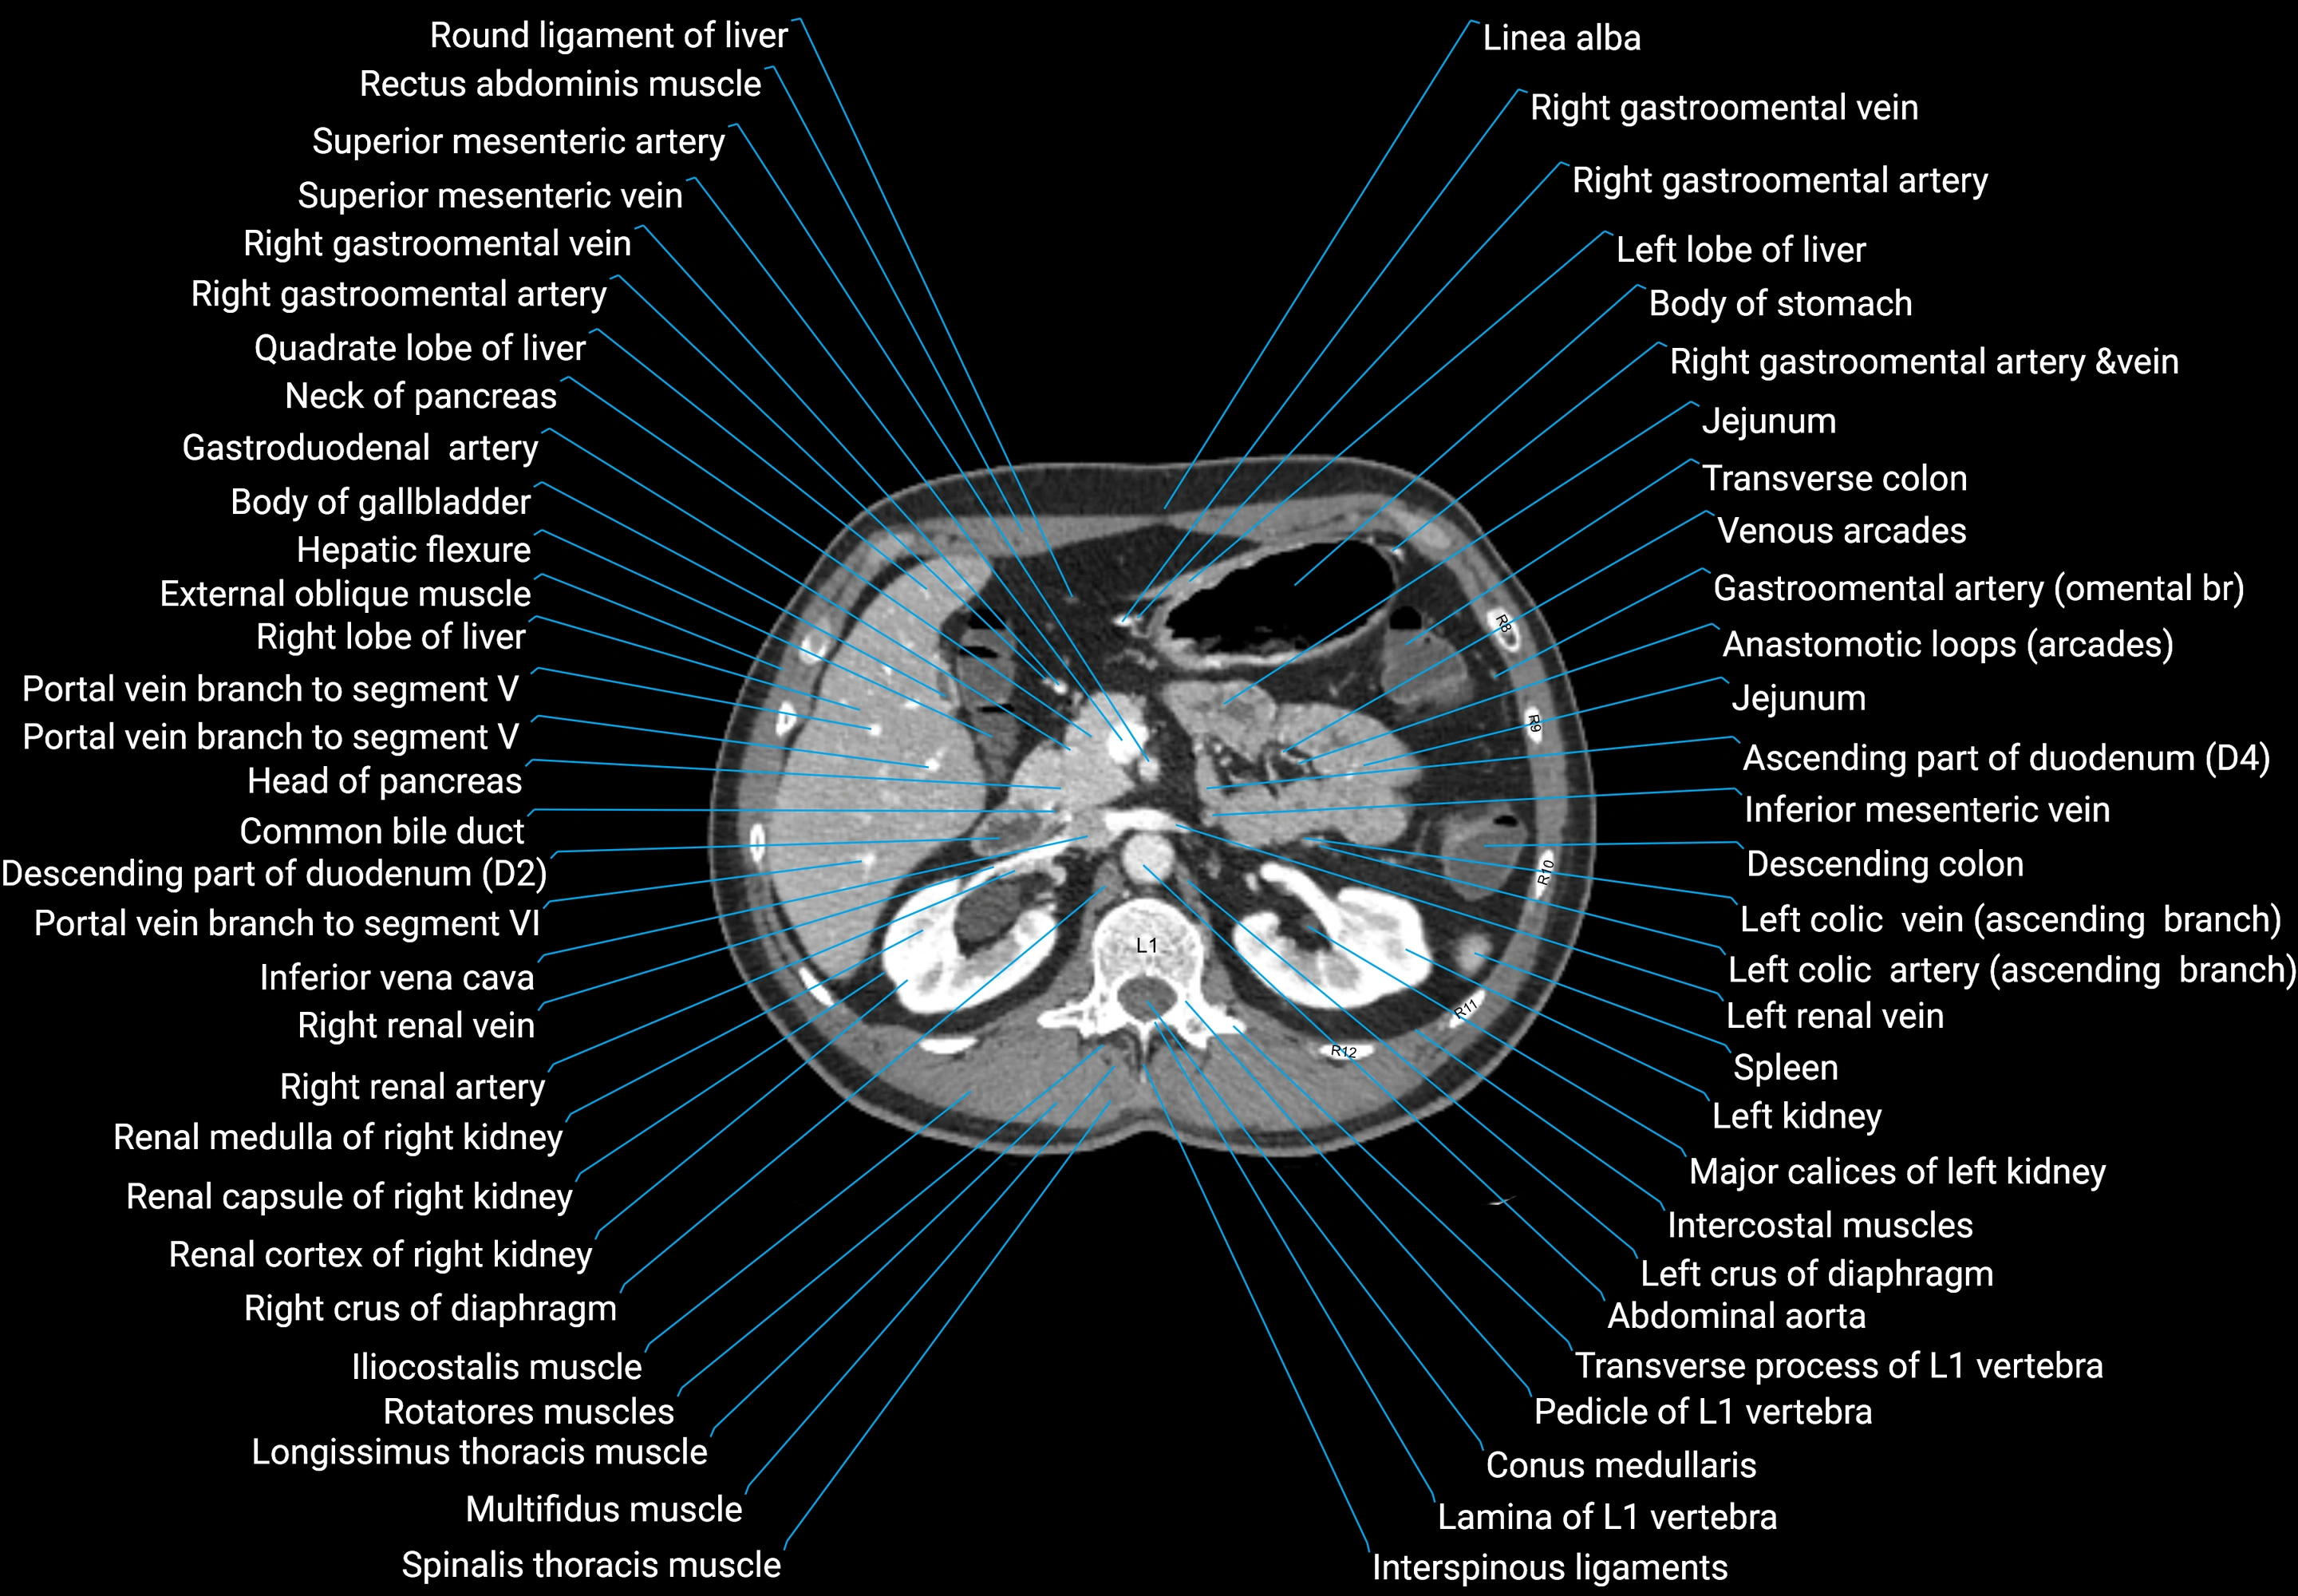

CT images